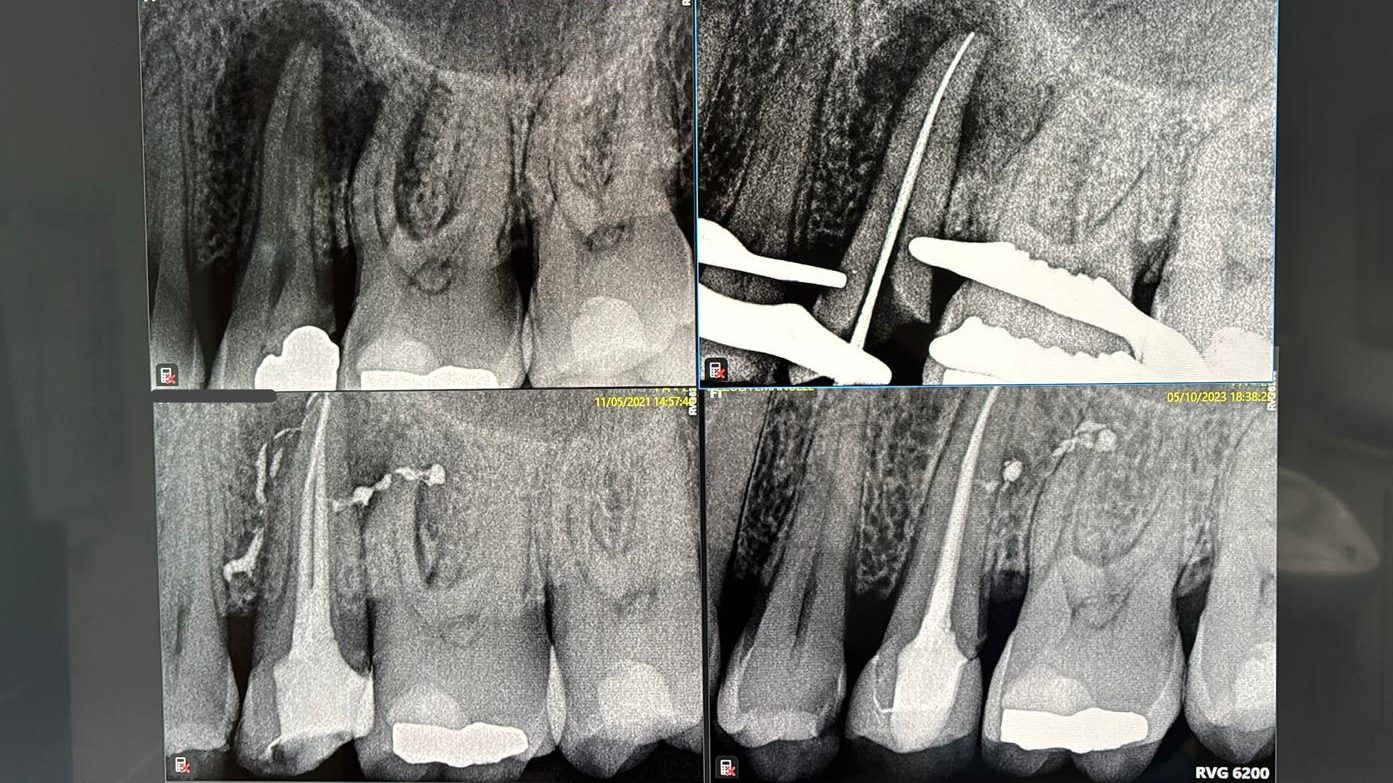

Radiografie endorali digitali

Mentre per quanto riguarda le immagini radiologiche intraorali l’utilizzo di un’apparecchiatura digitale permette di ridurre drasticamente l’ esposizione ai raggi X.